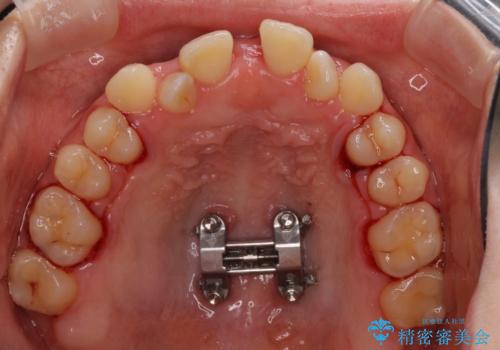

まずは急速拡大装置にて上顎骨を側方に拡大し、インビザラインにて歯列と咬合を整えることとしました。

上顎骨を拡大したことで、下顎の歯列を上顎が受け入れられるようになりましたが、インビザラインでは咬み合わせを改善させることができなかったため、ワイヤー矯正にて仕上げることとしました。